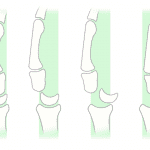

- Acute perilunate dislocation

- Perilunate dislocation

Discussion